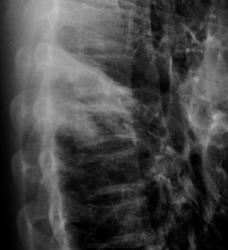

Томограммы дядюшки...

Формально фтизиатры поставят диагноз инфильтративный туберкулез S6 правого легкого, фаза распада. Но, я не зря спросил про возраст больного. У молодых людей нижнедолевой туберкулез особенно в 6 сегменте часто связан с поражением внутригрудных лимфатических узлов. Пути распространения инфекции лимфобронхогенное. Подтверждением этого является обнаружение при бронхоскопии различных форм активного туберкулеза (инфильтративный, язвенный и лимфобронхиальный свищ). При бронхоскопии у больного могут найдут специфическое поржение бронхов. Лимфогенный путь распространения напоминает раковый лимфангиит . О лимфогенном распространении инфекции указывает прединфильтратная сетка, которую хорошо видно на рентгенограммах. О поражении лимфатических бронхопульмональных узлов свидетельствует вовлечение в процесс плевральных листков в виде воспалительного уплотнения междолевой плевры, а также наклонность к раннему образованию распада. Известно,что у взрослых трудно выявить изменения со стороны ВГЛУ, так как они не часто достигают той величины, как у детей. Умеренно выраженное увеличение бронхопульмональных л/у на КТ диагностируется только при контрастировании. Таким образом, предварительный патогенетический диагноз звучал бы так : туберкулез внутригрудных лимфатических узлов бронхопульмональной группы справа, осложненный бронхолегочным поражением в S6 с распадом. Необходимо построить патогенетический диагноз, так как специфические изменения в лимфатических узлах требуют более длительного лечения. Такова моя точка зрения на диагноз у представленного пациента. С уважением Ваш NIkolas